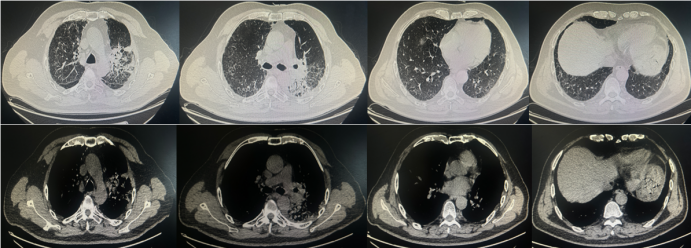

辅助检查:血常规示WBC 5.66×109/LNEU 5.19×109/L,LYM 0.22×109/L;Hb 114 g/L;SAA 249.9 mg/LCRP 79.9 mg/LIL-6 10.49 pg/mlPCT 0.1 ng/ml,血沉26 mm/h;血气分析PaO75.2 mmHgPaCO32.8 mmHg,氧合略低;GM试验、G试验、OT试验及新冠核酸检测均为阴性;呼吸道六项检查示肺炎克雷伯菌核酸及肺炎链球菌核酸均阳性。9月19日胸部CT示左肺门肿瘤伴周围炎症,双侧少量胸腔积液,左肺上叶及下叶实变影较前加重(图8)再次建议患者行气管镜检查。

图片

8  患者第三次住院期间胸部CT(2025-09-19)